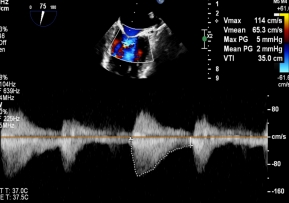

【图片1:术前超声图】

病例1为典型退行性二尖瓣脱垂(DMR),术前超声提示外交界瓣叶明显脱垂,反流程度达重度(4+),伴随活动后气促等心衰症状。由于病变位于“红区”,瓣叶结构复杂、对合不稳定,属于TEER治疗中的高难度类型。